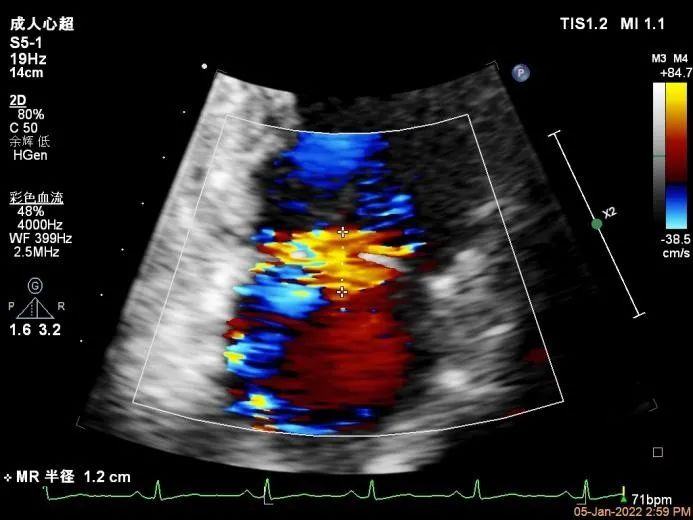

Bicom:MR(重度),返流束宽12mm,返流面积10.3cm2,PISA法定量EROA:

0.77cm2,Rvol:115ml,RF:35%,r:12mm。

Qlab软件勾画估测瓣口面积约:6.89cm2

二尖瓣口平均跨瓣压差:3mmHg